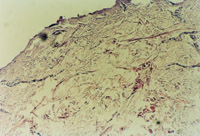

3-26 對(duì)大片的新生皮膚組織進(jìn)行組織學(xué)檢查,證實(shí)為生理性皮膚全層再生修復(fù)(傷后第49天)

3-27 已融合成新皮膚的區(qū)域,可見(jiàn)皮下組織大血管的解剖生理結(jié)構(gòu)形成